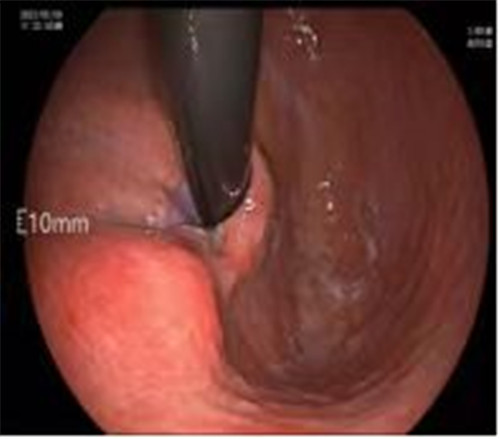

近期病例之一,圖片依次為:胃鏡、超聲胃鏡、ESE術(shù)中、術(shù)后、切下病變。